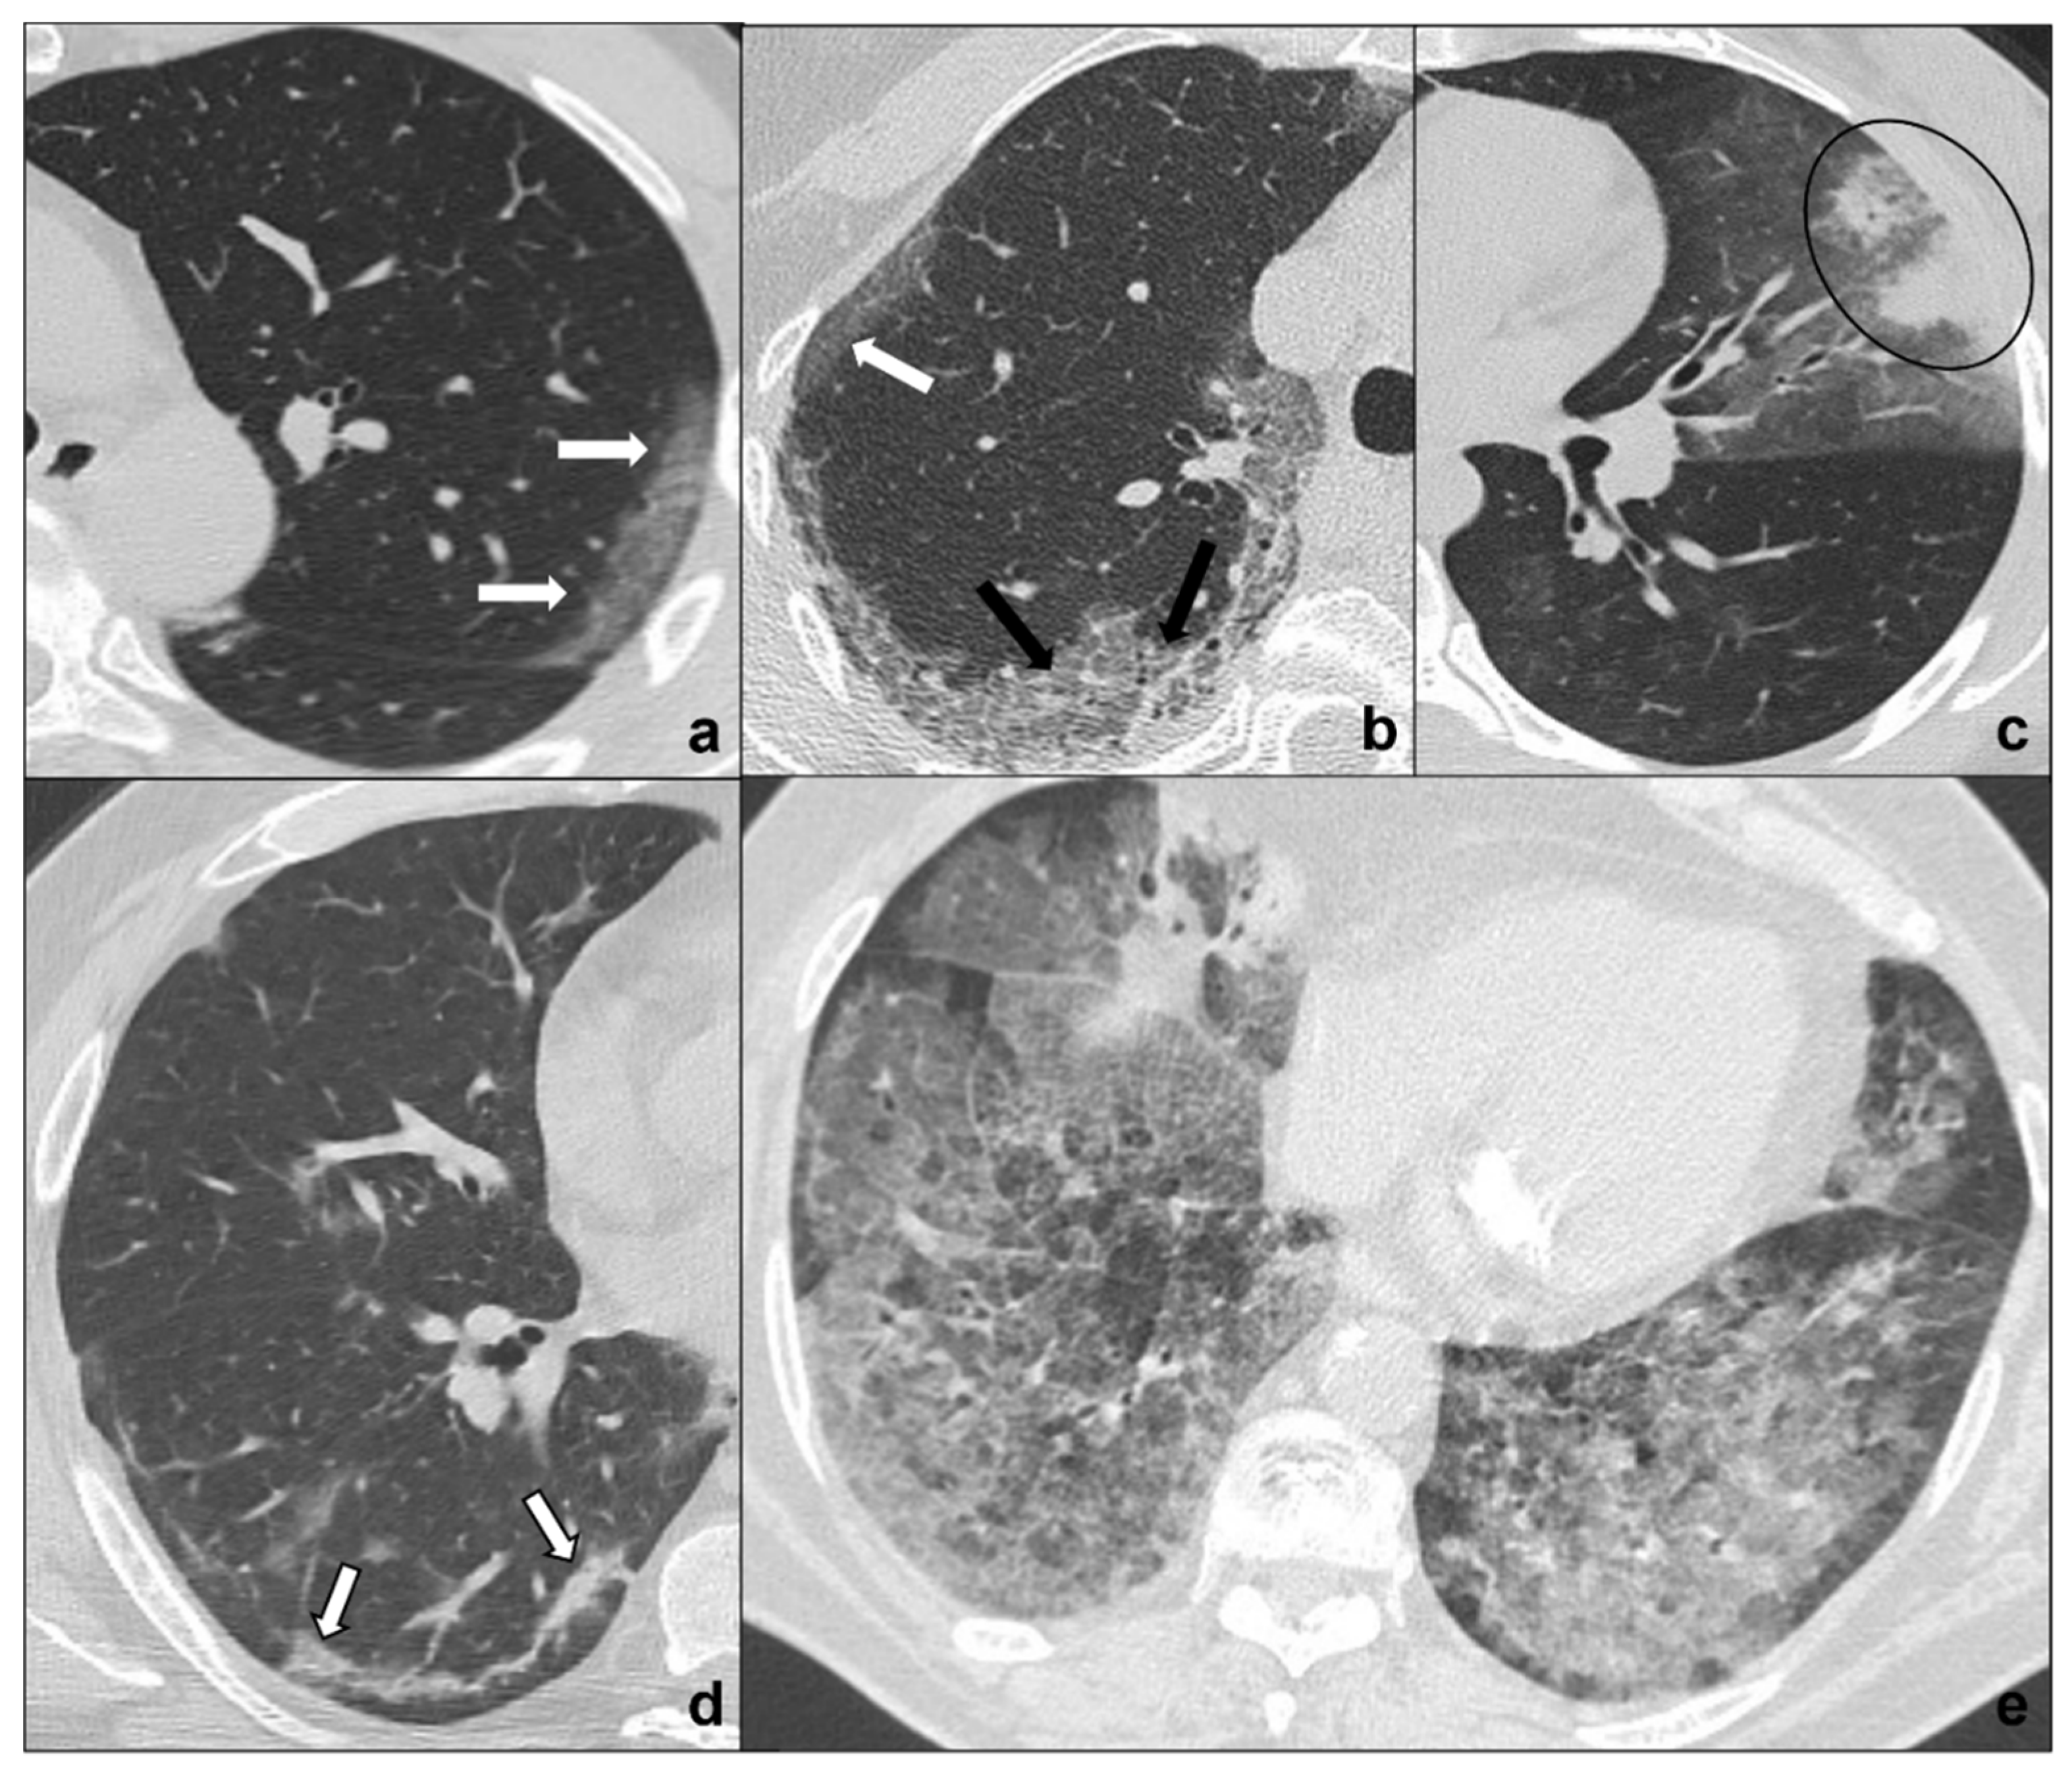

Figure 1.

(a–e) HRTCs showing the four different stages of COVID-19 pneumonia (a–d) and ARDS as a possible complication I. In (a), the first stage is characterized by subpleural ground-glass opacities (white arrows in (a,b)) which co-exist with extensive subpleural crazy paving pattern in stage 2 (black arrows in (b); in (c), consolidations (black circle) are typical of phase 3 and may be surrounded by ground-glass opacities; in (d) parenchymal bands (black-bordered white arrows in (d) are characteristic of the absorption phase); in (e), confluent ground glass opacities with dependent foci of consolidations represent a dire complication of COVID-19 pneumonia: acute respiratory distress syndrome. Lungs: mean window with 1500 HU; mean window level −600. Mediastinum: mean window with 350 HU; mean window level 50 HU.

- Early phase or phase one (between day 0 and day 4) is characterized by bilateral and diffuse subpleural ground-glass opacities (Figure 1a);

- Progressive phase or phase two (between day 5 and 8) shows extensive subpleural crazy paving areas co-existing with ground-glass opacities. Small consolidative foci may be present (Figure 1b);

- Peak phase or phase three (between day 9 and 13) is defined by subpleural consolidation with peripheral ground glass and/or crazy paving opacities (halo sign) (Figure 1c);

- Absorption phase or phase four (14 days and beyond) is the final stage in which parenchymal bands and ground-glass opacities represent a process of parenchymal repair and reorganization mediated by organizing pneumonia [27] (Figure 1d).

Patients may experience a sudden worsening of clinical conditions presenting with tachypnea, air hunger, and wheezing indicating a progression to a severe COVID-19 pneumonia complication: ARDS (acute respiratory distress syndrome) [30]. Chest CT shows patchy ground glass areas which progress to confluent opacities coexisting with dependent consolidations with a typical antero-posterior gradient [31].